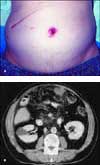

An 85-year-old man presented with intermittent abdominal pain of several years' duration. Two years earlier, he had undergone a laparoscopic cholecystectomy that was converted to an open procedure. A CT scan performed a year after surgery yielded normal findings.

The physical examination revealed an oozing mass that had been present for 3 weeks along the periumbilical area (A). Barium swallow and endoscopic examination results were unremarkable. A CT scan demonstrated multiple abdominal masses with invasion into the pancreas (B).

A biopsy of the node disclosed areas of squamous cell carcinoma and adenocarcinoma; the periumbilical mass was a Sister Mary Joseph nodule. Immunohistochemistry stains demonstrated cytokeratin 7 and carcinoembryonic antigen. No clear primary source of the malignancy was discovered; the differential diagnosis included malignancy from the pancreas, colon, and bile duct.

Because of the extent of the disease and the poor prognosis, this patient was given palliative chemotherapy. He died 3 months later.